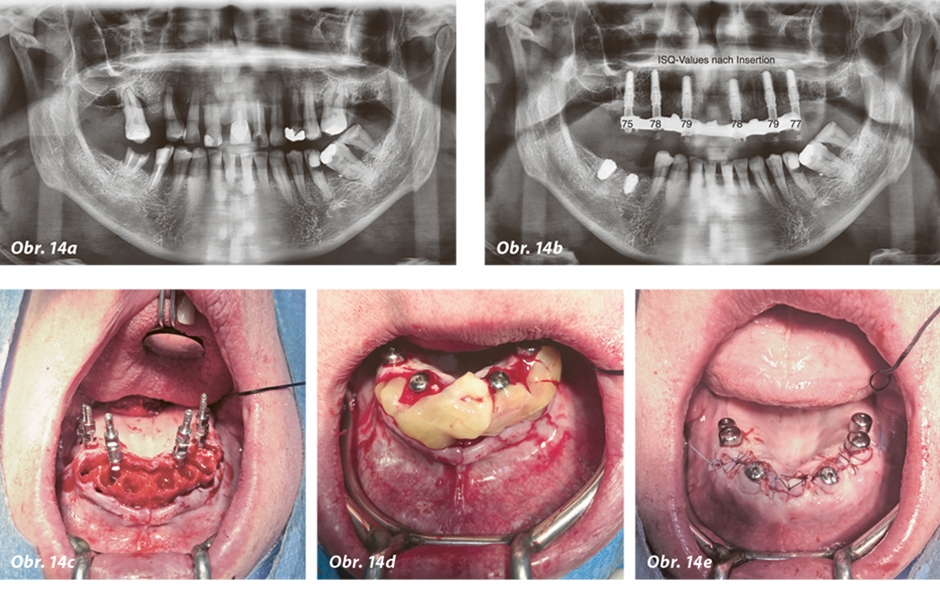

Obr. 14a–e: Případ pacienta s implantáty v modifikované pozici zavedenými technikou „all on 6“.

Tato varianta implantátů podstatně usnadňuje chirurgické procedury. Je výrazně jednodušší zavést čtyři, pět nebo šest implantátů, jsou-li paralelní. Ukázku, jak tato modifikovaná koncepce „all on X“ funguje u implantátů AnyRidge v konkrétním klinickém případu, vidíte na obrázcích 14a–j, na kterých je zachycena koncepce „all on 6“.

Použití metody rezonanční frekvenční analýzy (RFA) se osvědčilo u speciálních malých abutmentů (SmartPegs) a poskytuje vědecký základ pro posouzení stability implantátu a jeho nosnosti. Hodnota ISQ, která je výsledkem uvedeného měření, se proto jeví v raném stadiu jako přiměřeně reprezentativní pro odhad stability implantátu (obr. 16). Díky řezným závitům navíc implantát často vykazuje při zavádění podstatně větší síly, a tudíž vynikající primární stabilitu. Díky samořeznému mechanismu závitů implantáty AnyRidge obvykle vykazují velmi dobrou primární stabilitu, a to i u velice měkkých typů kostí. To znamená, že chirurg může po zavedení implantátu počítat s uspokojivými hodnotami ISQ.

V podobě metody rezonanční frekvenční analýzy máme navíc k dispozici nástroj, který nám často umožňuje validovat naše klinické procesy z hlediska managementu kvality. Příklad typické hodnoty ISQ u implantátů AnyRidge zavedených do kosti typu II/II je:

- ISQ 75–78 při prvotním měření po zavedení implantátu

- ISQ 78–82 při druhém měření po šesti týdnech od zavedení

- ISQ > 82 při třetím měření po šesti měsících od zavedení